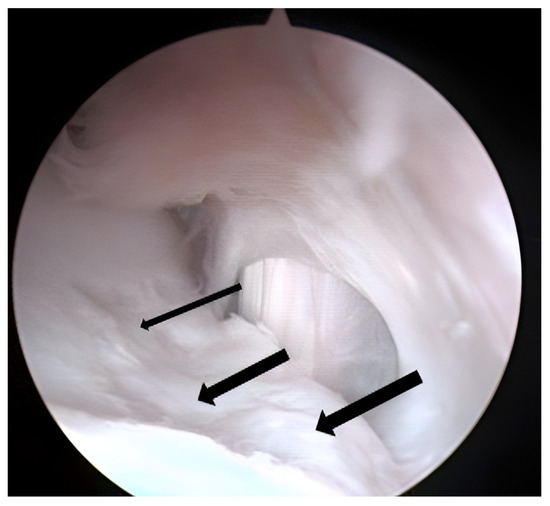

3.2. Arthroscopic Evaluation of the Lesion Site